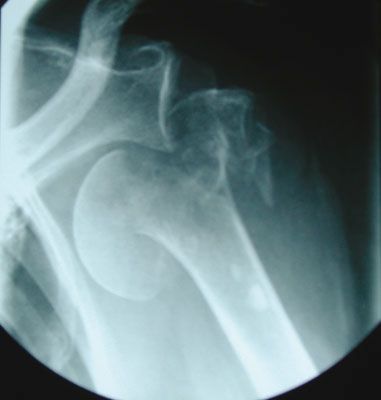

Arthroplastie inversée de grammont en traumatologie fraîche gériatrique